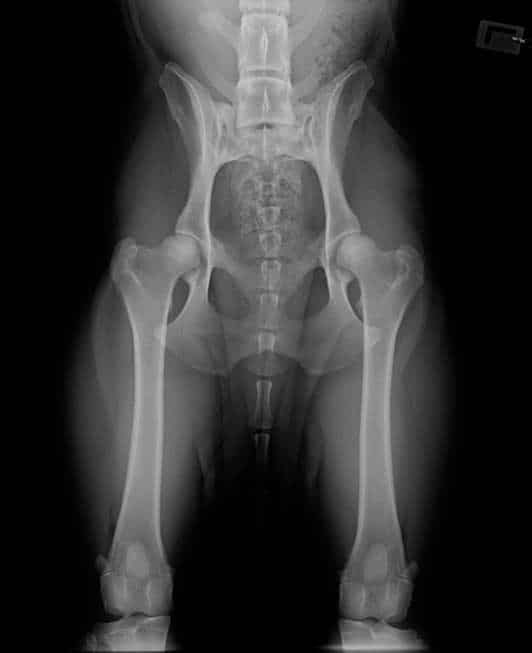

Ultralydsscanning i dyrlægepraksis

Ultralydsscanning er et skånsomt og værdifuldt redskab i moderne veterinær medicin. Det bruges til at

undersøge dyrets indre organer i realtid – helt uden kirurgi, stråling eller bedøvelse i langt de fleste

tilfælde.